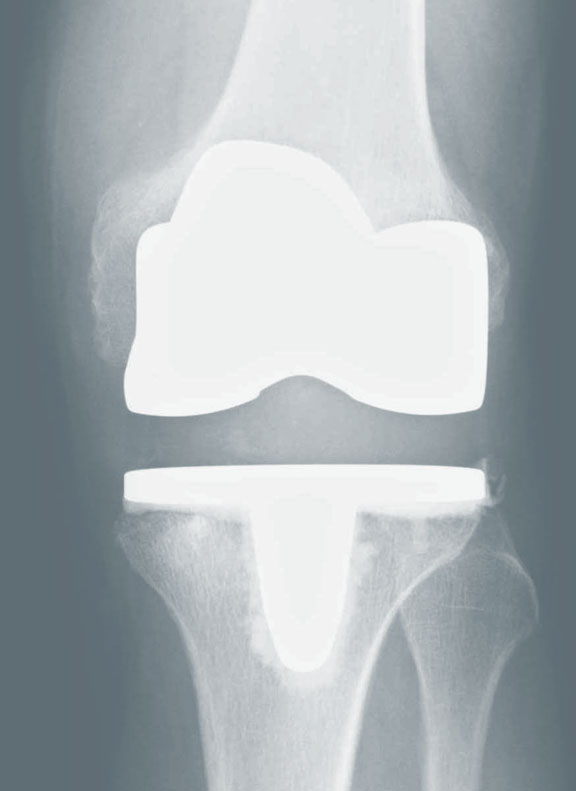

Ist Ihr Gelenkverschleiß zu weit fortgeschritten und Ihre Mobilitätt in der Folge stark eingeschränkt können wir Ihnen durch die Implantation eines Kunstgelenkes (Endoprothese) Lebensqualität zurückgeben.

Die endoprothetische Versorgung unserer Patienten erfolgt durch auf dem Gebiet der Endoprothetik spezialisierte Ärzte. Wir können Ihnen die notwendige Routine bei der Versorgung der Hüft-, Knie- und Schulterarthrose mittels eines Kunstgelenkes bieten. Einen großer Vorteil stellt bei einer Versorgung in unserer Praxis die Möglichkeit der jahrelangen ambulanten Nachbehandlung durch Ihren Operateur dar, welche in vielen Kliniken heutzutage nicht mehr möglich ist. Der Eingriff selbst findet in der nahegelegenen Havelklinik statt, welche in Berlin zu einem der ersten endoCert® zertifizierten EndoProthetikZentren (EPZ) gehört und durch jährliche Rezertifizierungen einen hohen Qualitätsstandard im Bereich der Endoprothetik erfüllt. Zur postoperativen Überwachung besitzt die Klinik auch eine IMC-Station (Wachstation).

Die endoprothetisch versierten Ärzte der Biberburg sind alle Hauptoperateure des EPZ.